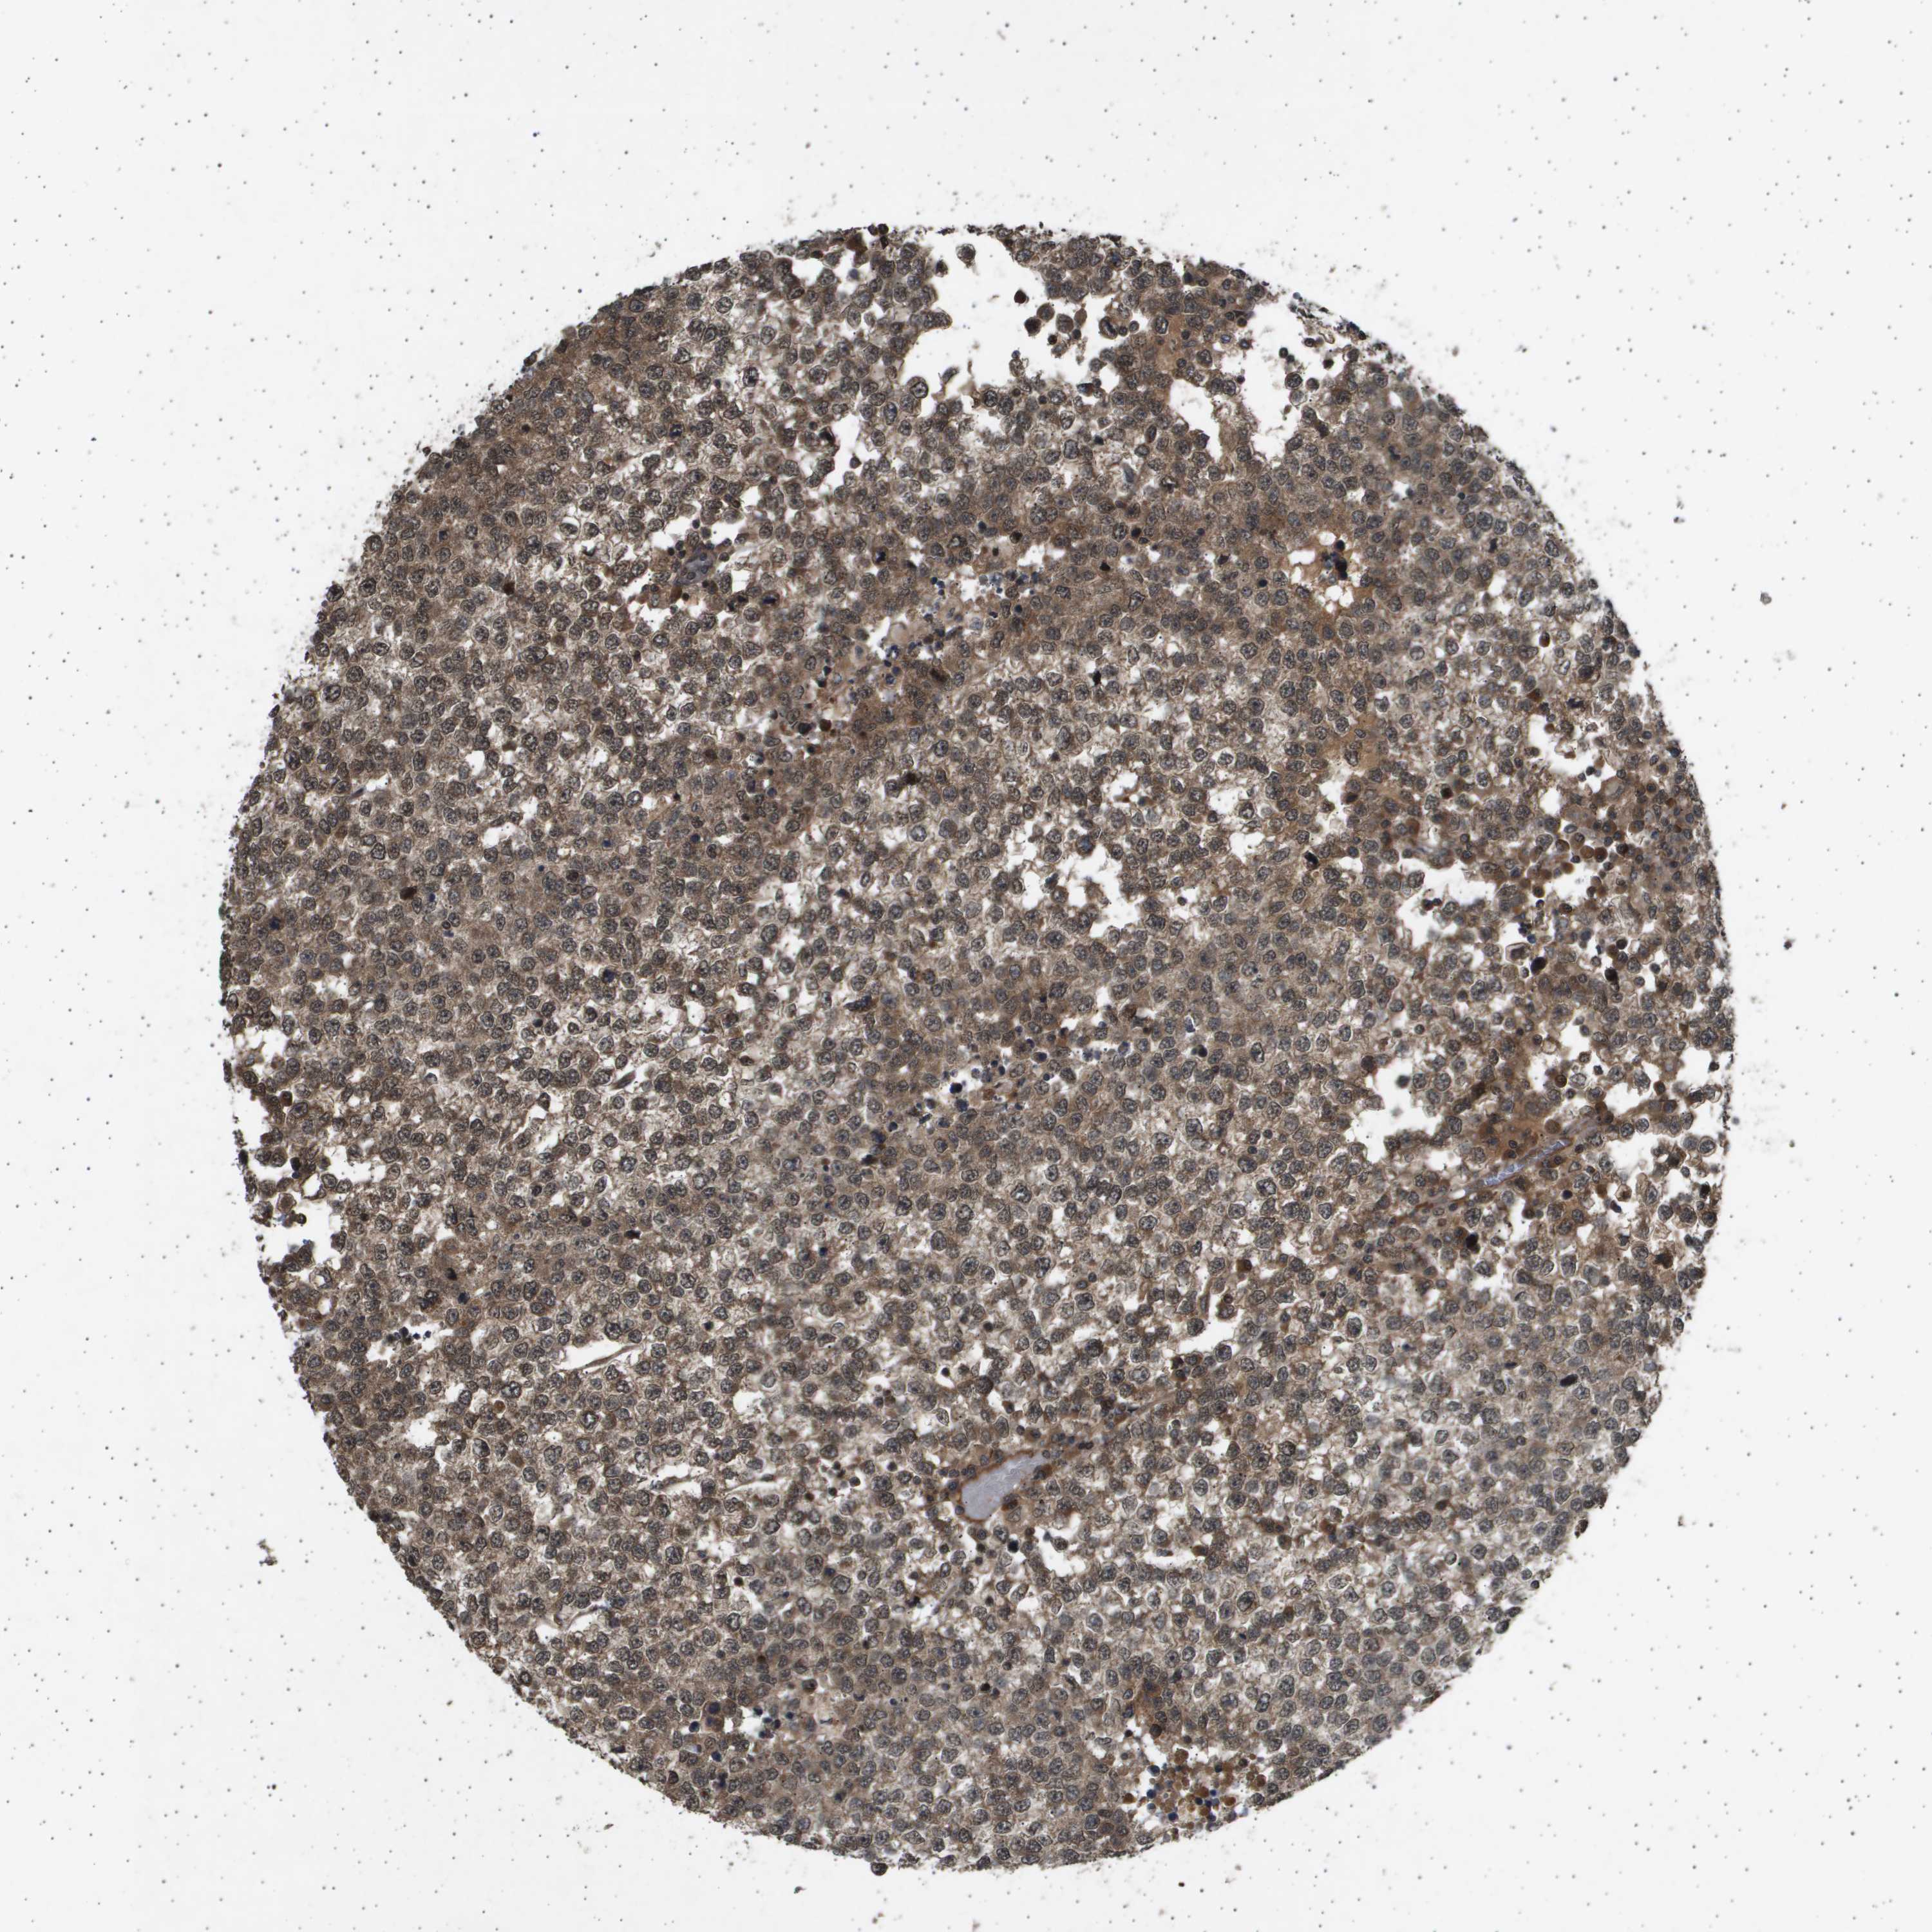

TESTIS CANCER - Protein expressioni

A mouse-over function shows sample information and annotation data. Click on an image to view it in a full screen mode. Samples can be filtered based on level of antibody staining by selecting one or several of the following categories: high, medium, low and not detected. The assay and annotation is described here.

Note that samples used for immunohistochemistry by the Human Protein Atlas do not correspond to samples in the TCGA dataset.

Antibody stainingi

Antibody staining in the annotated cell types in the current human tissue is reported as not detected, low, medium, or high, based on conventional immunohistochemistry profiling in selected tissues. This score is based on the combination of the staining intensity and fraction of stained cells.

Each image is clickable and will lead to virtual microscopy that enables deeper exploration of all samples and also displays staining intensity scores, fraction scores and subcellular localization as well as patient and tissue information for each sample.

Antibody HPA017869

Staining

High

Medium

Low

Not detected

Intensity

Strong

Moderate

Weak

Negative

Quantity

>75%

75%-25%

<25%

None

Location

Nuclear

Cytoplasmic/membranous

Cytoplasmic/membranous,nuclear

Carcinoma, Embryonal, NOS

Seminoma, NOS